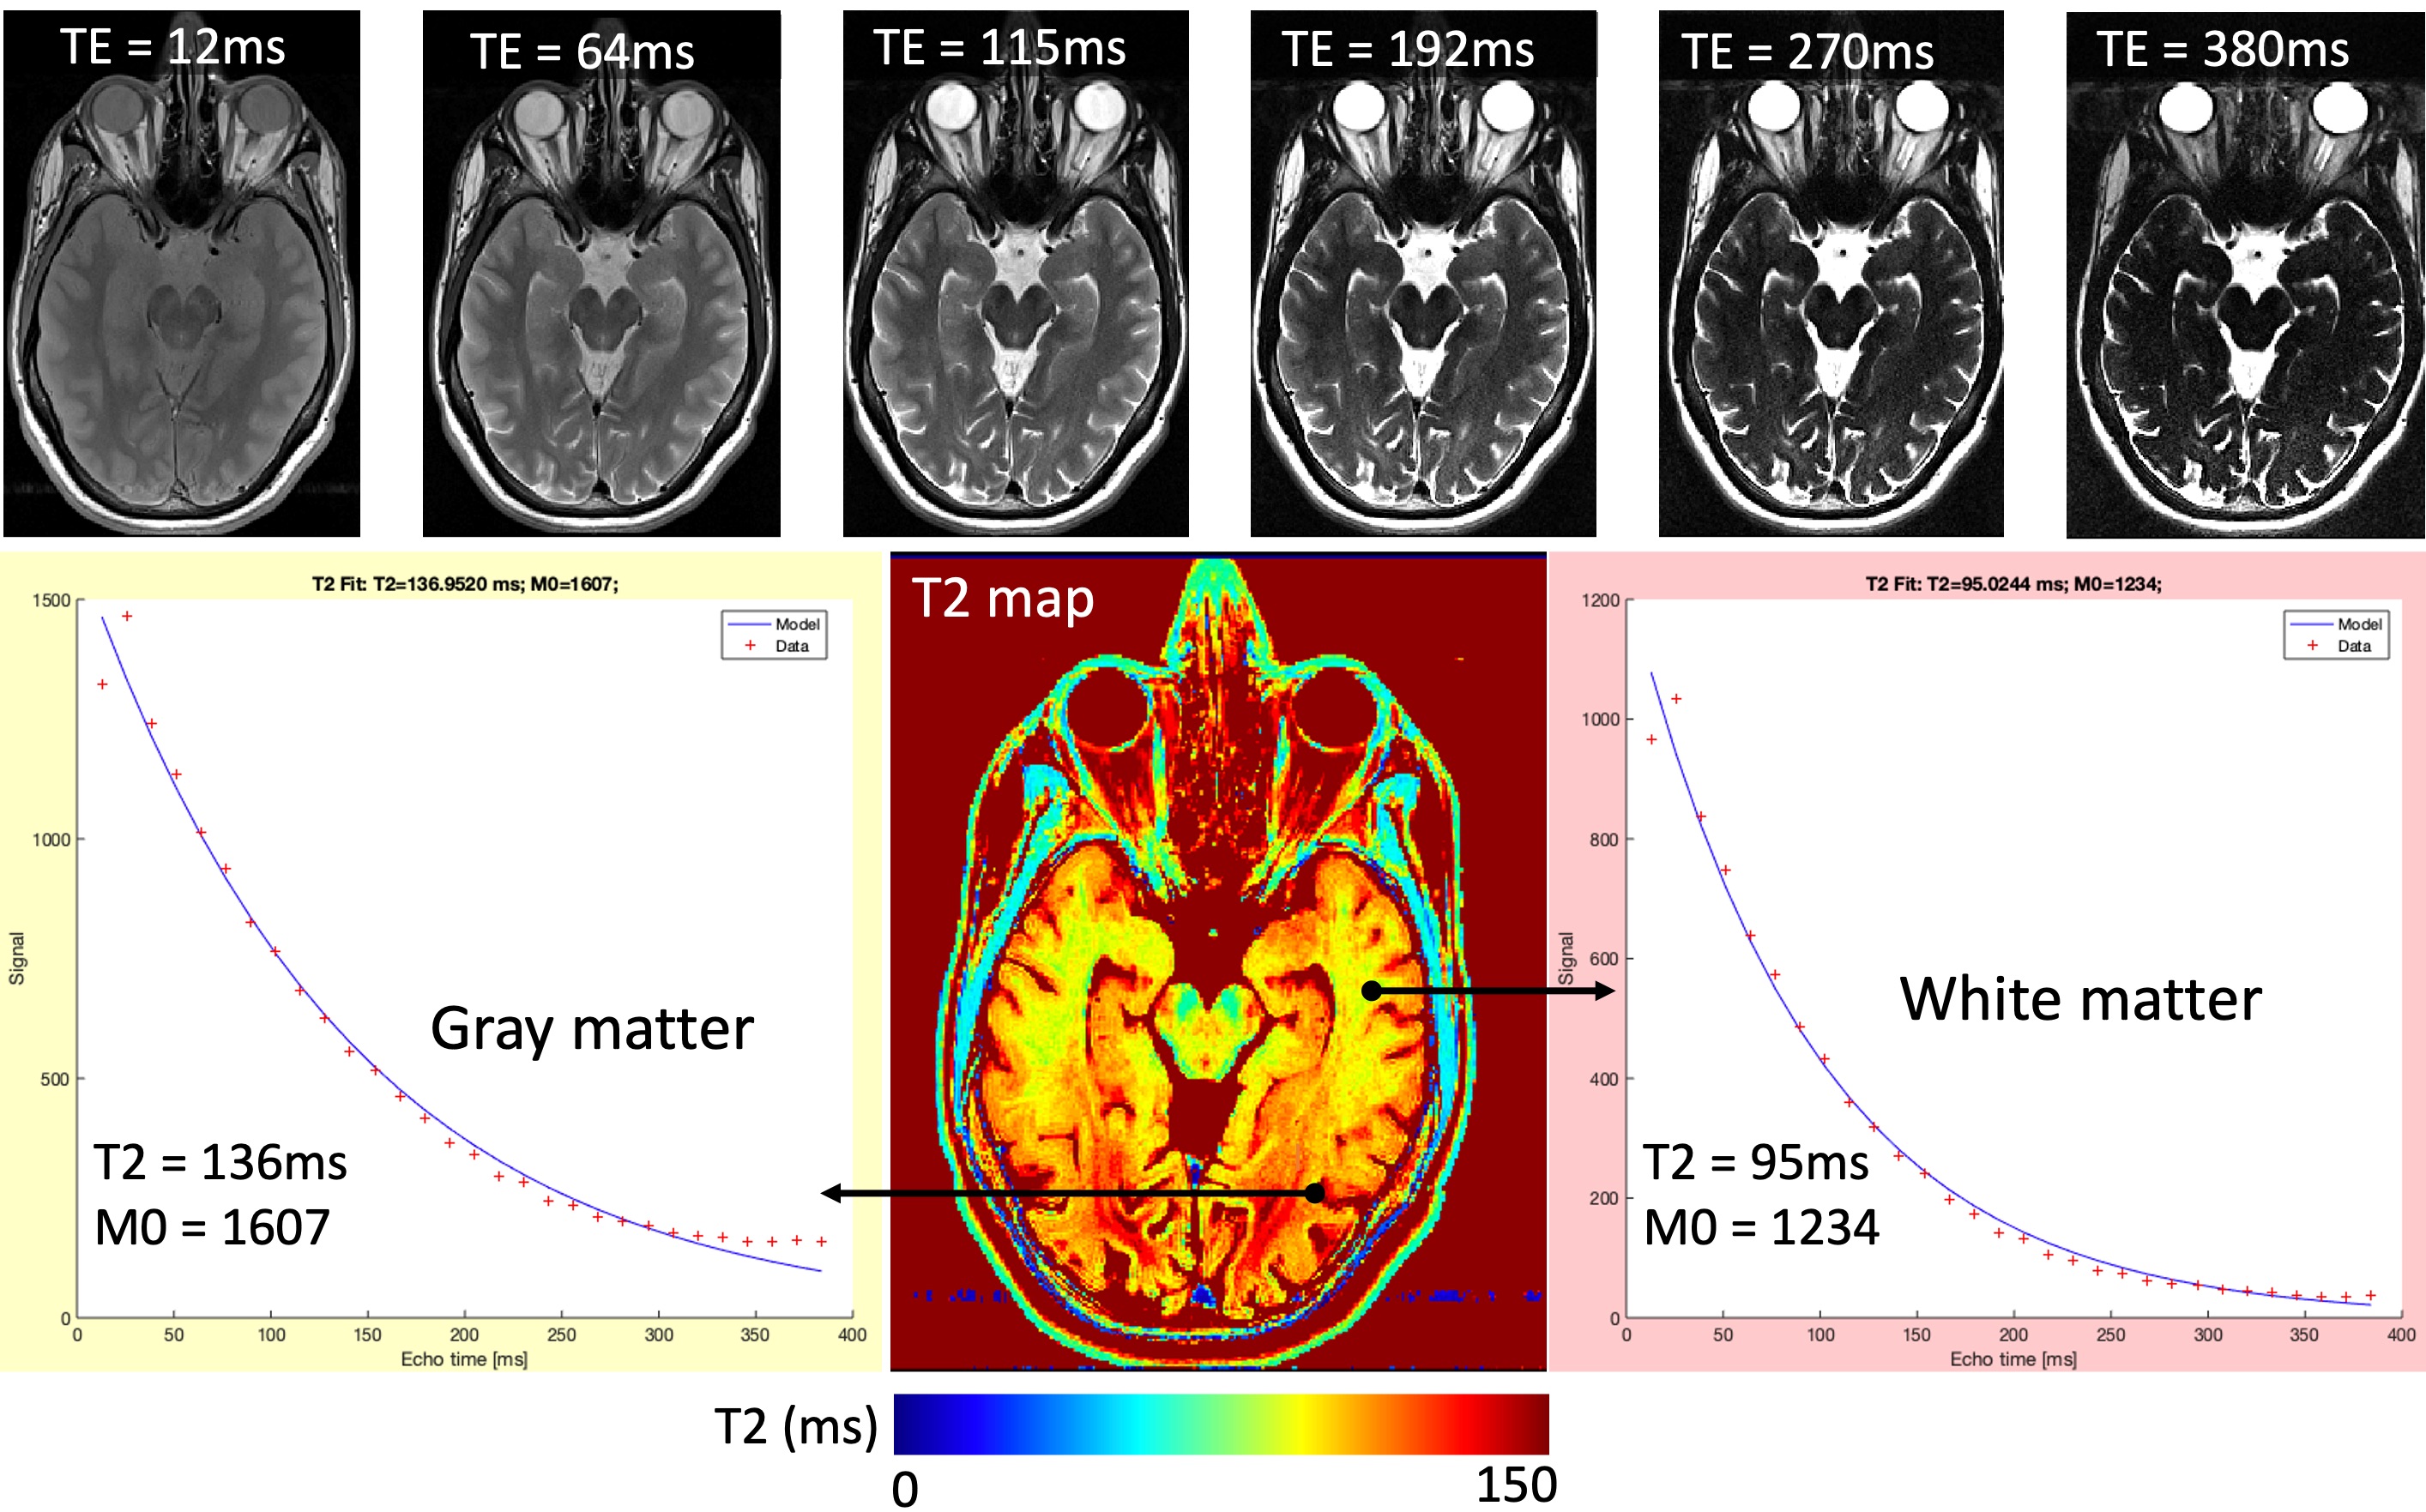

), the exponential in the second term of the equation converges to zero, reducing the T1 contribution. Therefore when the TE is short and the TR is long, the contribution to image contrast comes from the density of the spins, i.e. proton density. On the other hand, to increase the T2-weighting by keeping TR the same (long), the TE must be increased (the importance of the last term increases). Figure 17 exemplifies this by showing the same image across 6 echoes, where substances with longer T2 (e.g., eyes and the cerebrospinal fluid (CSF)) appear gradually brighter compared to the other structures in the image as the TE increases.

Figure 17:An example T2 map, estimated by fitting voxel-wise brightness values (red plus signs) across 32 echo times

to the exponential decay (blue line) defined by Equation Eq. 4. The top row shows how conventional image contrast changes from proton-density to T2-weighted as the TE increases from 12ms to 380ms.

Since the signal representation is known for the basic SE acquisition, the signal (the voxel brightness) can be sampled at several TE’s and fitted to the exponential decay defined by the last term of the equation to calculate T2, namely T2 mapping. The second term of the equation will not be taken into account, as the TR will be kept constant across the samples. Figure 17 shows a T2 mapping example, where an axial image of the human brain was collected across 32 TE’s ranging from 12 to 380ms.